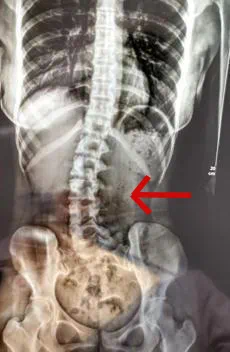

习惯侧身趴着睡其实很伤脊椎